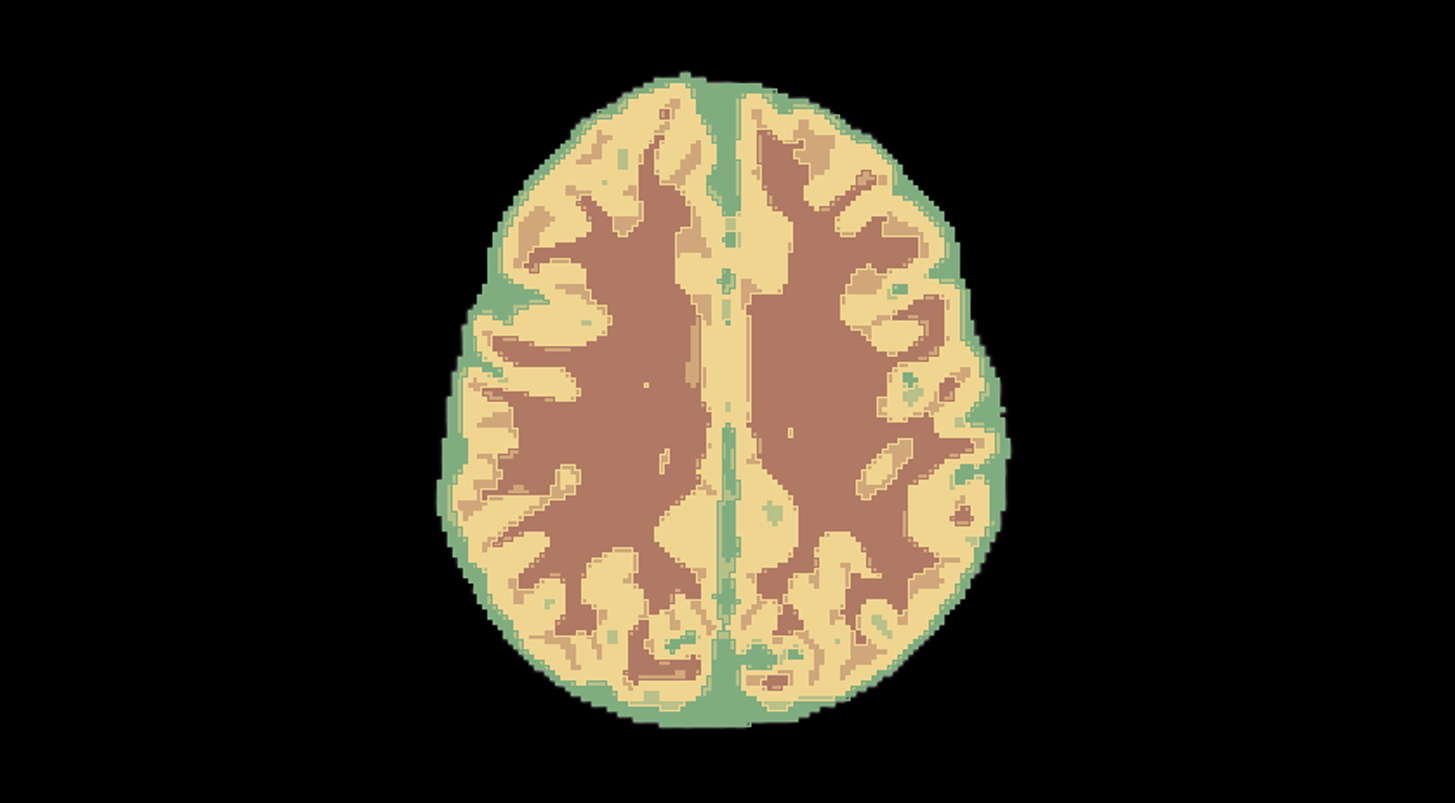

Вот как это работает на валидационной выборке. Исходное исследование из выборки:

Пример работы алгоритма:

Решение автоматически определяет на каждом срезе МРТ, где находится серое и белое вещество, с определённой долей вероятности.

Из таблицы можно перейти в само исследование, где уже выделены маски белого и серого вещества: